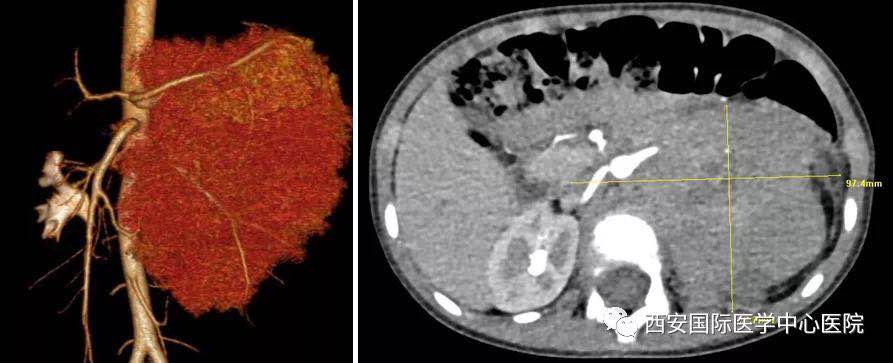

入院后,楊增悅主任仔細(xì)詢問病史、查閱影像學(xué)資料,第一時(shí)間為依依安排骨髓穿刺活檢,最終確診為:腹膜后神經(jīng)母細(xì)胞瘤(Ⅳ期/L2)。CT顯示腫瘤巨大,侵及腹主動脈、腹腔干、腸系膜上動脈、雙腎動脈、腸系膜下動脈、下腔靜脈、雙腎靜脈、左腎及腎上腺、胰十二指腸、脾臟、結(jié)腸脾曲;腹膜后多發(fā)淋巴結(jié)轉(zhuǎn)移、骨轉(zhuǎn)移。骨穿病檢示:神經(jīng)母細(xì)胞瘤骨髓轉(zhuǎn)移,腫瘤細(xì)胞占90.5%。經(jīng)過科室團(tuán)隊(duì)討論后決定,先行新輔助化療后再進(jìn)行手術(shù)治療。